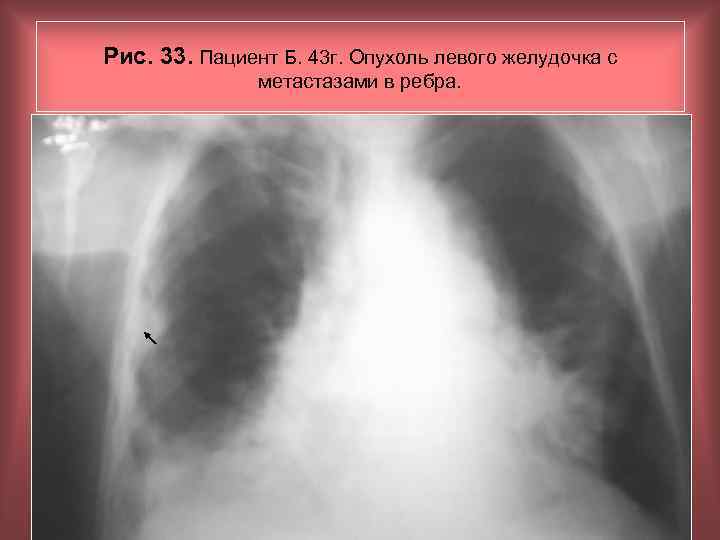

Рис. 33. Пациент Б. 43 г. Опухоль левого желудочка с метастазами в ребра. Н. С. Воротынцева, С. С. Гольев Рентгенопульмонология